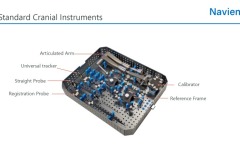

Cranial, Biopsy, Spine, ENT

Tracking system

• Infrared optical tracking system

• Live video stream

• 0.2mm calibration accuracy

• Permanent markers

• Reusable and sterilizable instruments